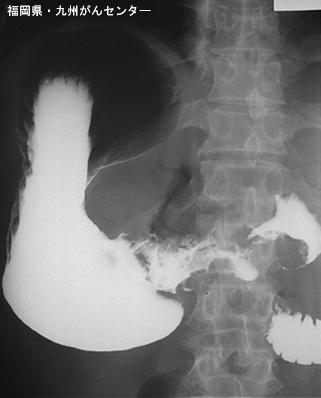

Posted by: Fukuoka Pref., 九州癌中心

部位(按器官分)胃(部位)/2个以上

检查方法X线

肿瘤的肉眼分类3型(溃疡浸润型)/

肿瘤最大直径40以上

肿瘤的深度s(a)